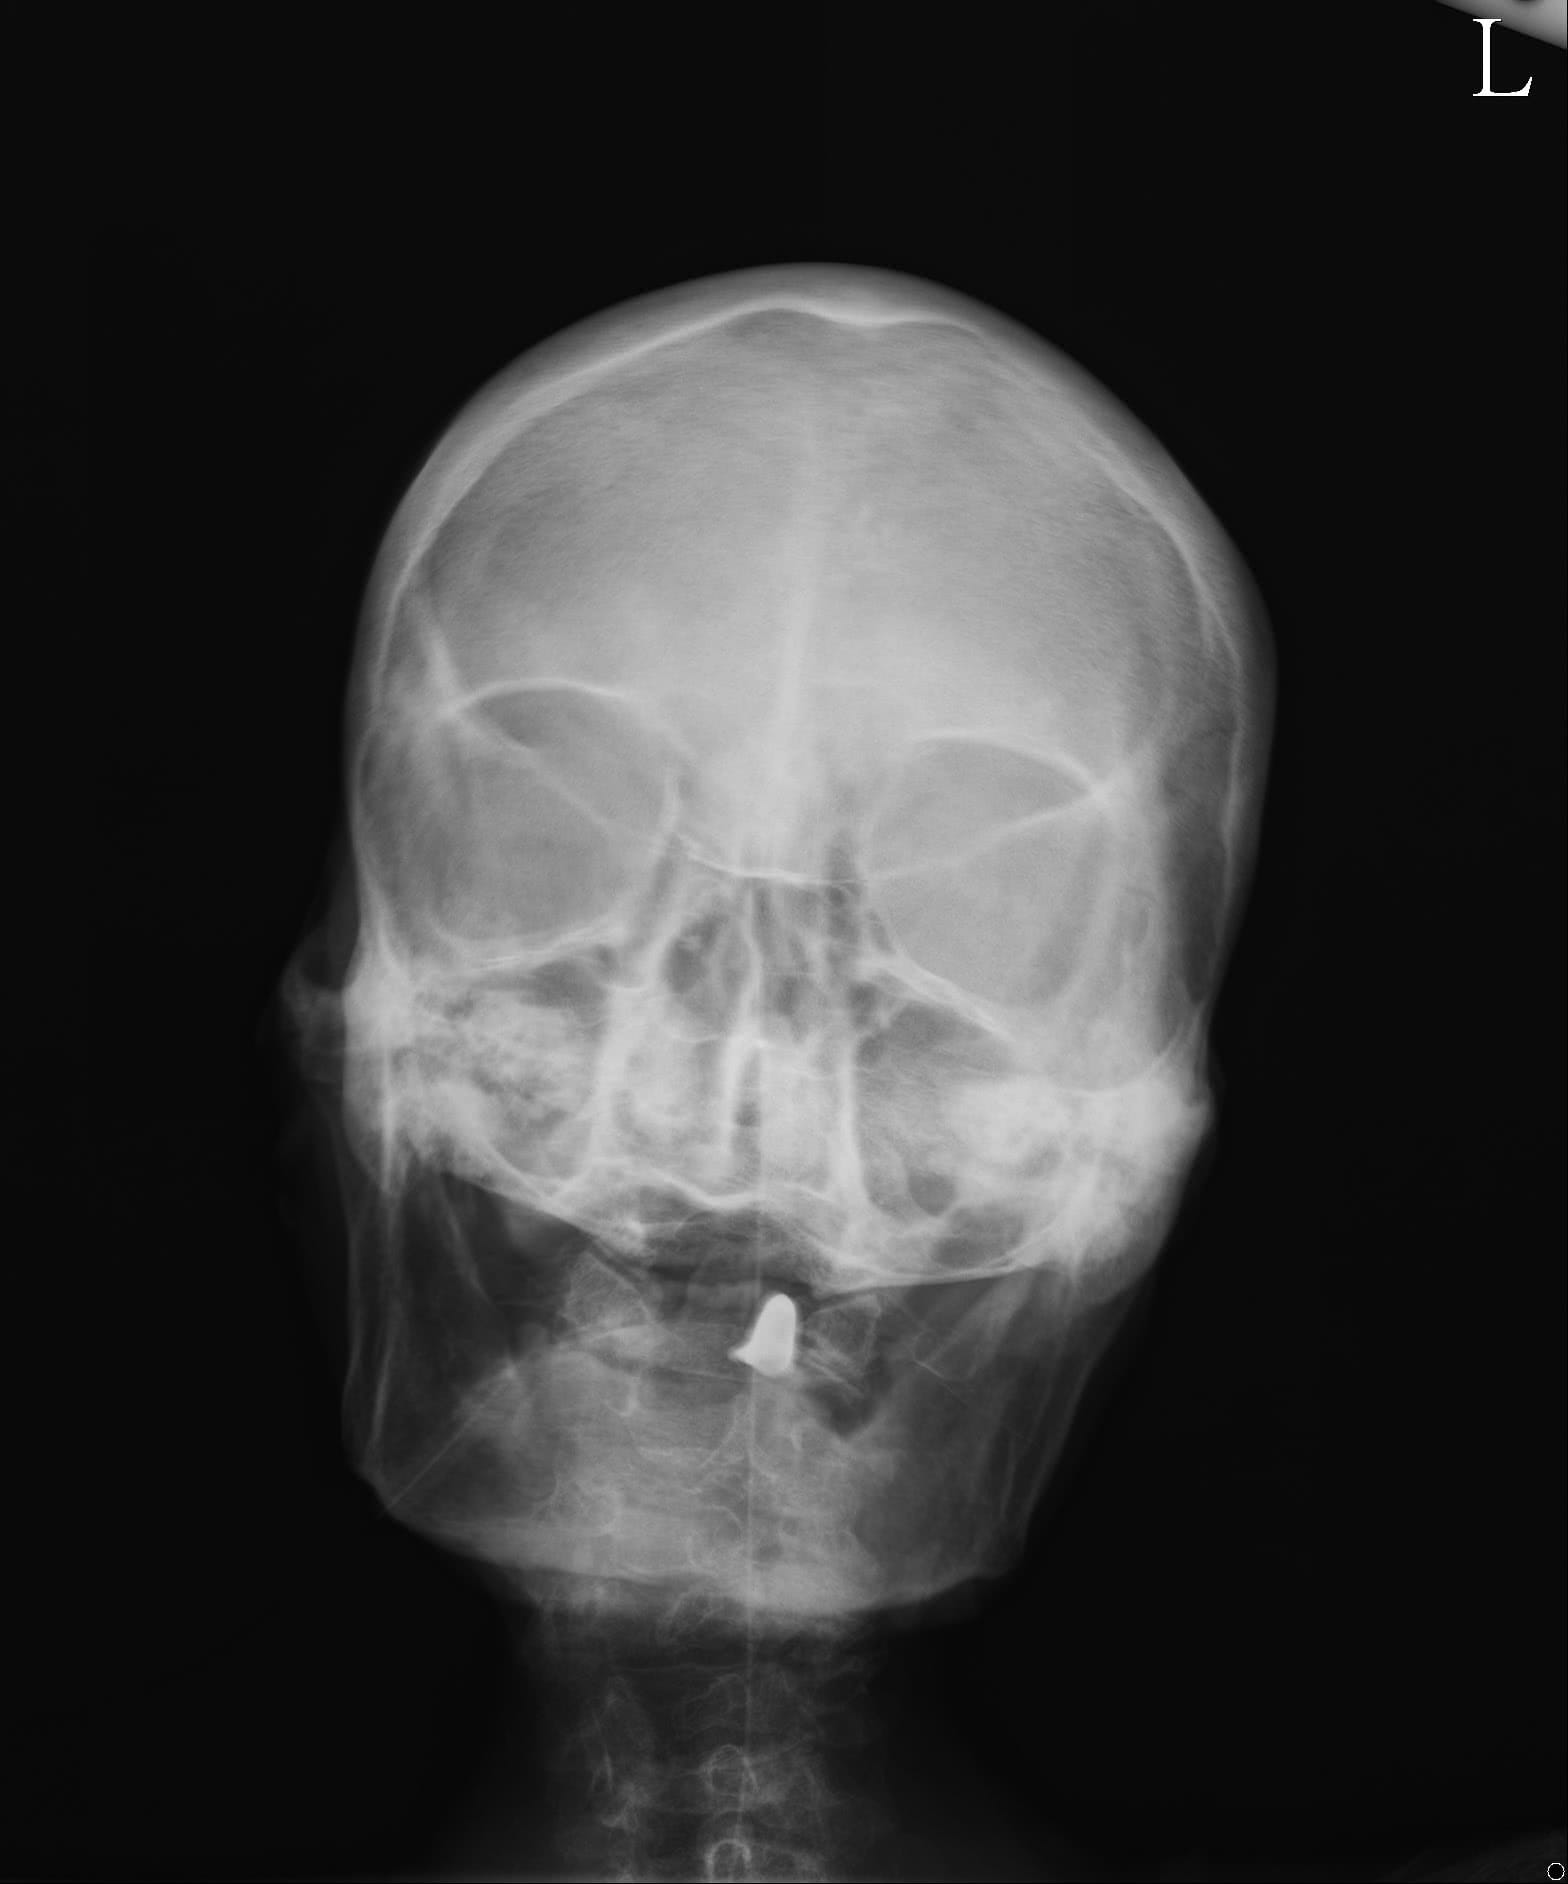

驗了 IFE (免疫固定電泳分析),發現 IgA, IgG 皆有增加情況,為 polyclonal pattern, 較不像 Multiple myeloma 的 monoclonal pattern ,而檢驗了頭骨 X-ray 也並沒有發現 Multiple myeloma 的蝕骨病灶。驗了 kappa/lamda ratio, 也是正常。